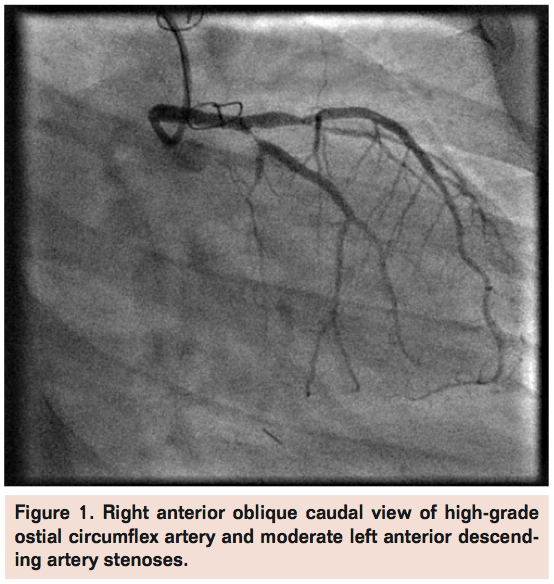

Case 1. A 14-year-old female with history of orthotopic heart transplantation 7 years prior for primary dilated cardiomyopathy was referred for PCI from Children’s Hospital Boston. Routine post-transplant angiography 1-week prior to PCI revealed progressive CAV with a newly noted high-grade proximal left circumflex stenosis (Figure 1). She had been complaining of chest heaviness and shortness of breath with moderate exertion. The patient weighed 105 lbs (47.7 kg) and her height was 62 inches (158 cm). She had prior cardiac catheterizations via femoral access without major complications. Her medications included aspirin, diltiazem, enalapril, furosemide, spironolactone, pravastatin, tacrolimus, and mycophenolate. She received a loading dose of clopidogrel 300 mg the day before her planned PCI. The modified Allen’s test utilizing plethysmography of the left radial artery was normal (Grade A).